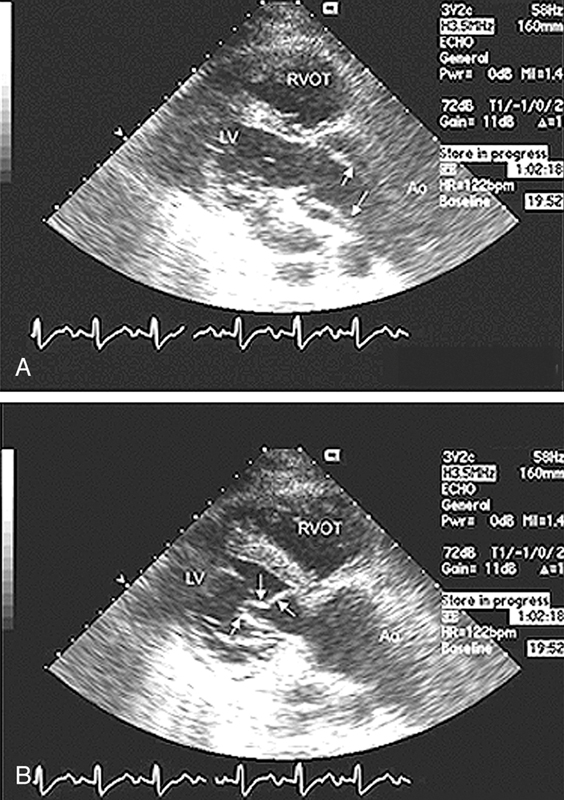

فحوصات تشخيصية لبعض امراض القلب والشرايين التاجية